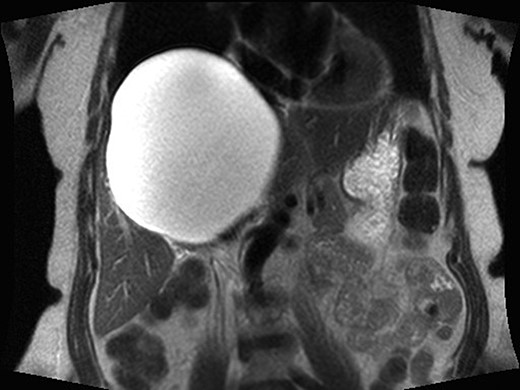

A 68-year-old female had a known hepatic cyst for about 3 years. It had been previously noted on abdominal CT but was not symptomatic at the time of discovery. Upon developing gastroesophageal reflux-type symptoms, pressure-like abdominal pain, right upper quadrant pain, fullness and nausea, she was referred for surgical evaluation. Physical exam was significant for palpable liver edge below the costal margin, but the abdomen was non-tender. This prompted further work-up, revealing elevated liver enzymes and a 16 cm × 14 cm cystic hepatic lesion on magnetic resonance imaging (MRI), consistent with a simple cyst (Fig. 1). An aspirate of the contents was obtained and sent for culture, gram stain, bilirubin, CEA levels and CA-19-9, all of which were within normal limits. Owing to the patient's discomfort, surgical fenestration and ablation of the remaining cyst wall were recommended. A single-incision laparoscopic approach was offered to the patient, and the patient consented to proceed.